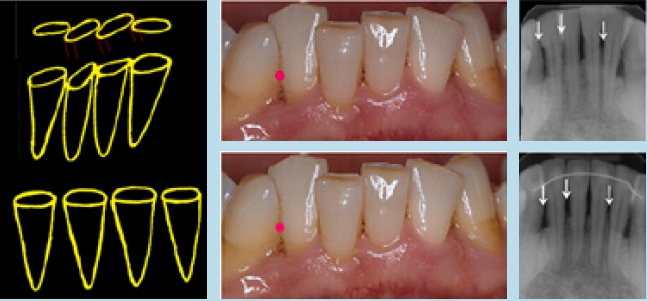

Der Approximalraum ist ein dreieckiger Raum, der von Gingiva ausgefüllt und von den 2 Approximalflächen der benachbarten Zähne und dem Alveolarknochen begrenzt wird (Abb. 1). Eine Änderung des Approximalkontaktes in Höhe und Form führt in der Regel zu einer Änderung des Approximalraums und dessen Auffüllung mit der Interdentalpapille. Tarnow et al. konnten bei ihrer Studie den Zusammenhang zwischen der Größe des Approximalraums und der Distanz zwischen der Crista alveolaris und dem Kontaktpunkt nachweisen [27]. Je größer die Distanz ist, desto größer ist der Approximalraum und desto weniger ist dieser Raum mit Papille aufgefüllt. Wenn der Abstand 3, 4 oder 5 mm beträgt, ist die Papille bis zu 100% vorhanden (Abb. 2a). Bei einer Distanz von 6 mm ist die Hälfte der Papille vorhanden (Abb. 2b). Wenn die Distanz mehr als 7, 8, 9 oder 10 mm beträgt, ist die Papille in der Regel nicht vorhanden (Abb. 2c, Abb. 3a und b). Dieser Effekt kann in der Kieferorthopädie zur Verbesserung der dentogingivalen Ästhetik insbesondere bei Patienten mit parodontal geschädigten Zähnen und vergrößertem Approximalraum (dunkles Dreieck) ausgenutzt werden. Durch das Strippen der Zähne und das Schließen des entstehenden Raumes kann der Kontaktpunkt weiter zervikal verlegt werden. Dadurch wird die Distanz zwischen Kontaktpunkt und Knochenrand verkleinert. Als Resultat füllt sich der Approximalraum mit mehr Papille auf, was eine sofortige Verbesserung des Erscheinungsbildes bewirkt. Zudem führt längerfristig die Verringerung des Abstandes zwischen Kontaktpunkt und Alveolarknochen zu einem geringeren Risiko hinsichtlich der Entstehung gingivaler Rezession [27] (Abb. 4a bis c).

Hier muss zwischen einer Schmelzreduktion an korrekt stehenden Zähnen und einer an malpositionierten Zähnen unterschieden werden. Bei korrekt angeordneten Zähnen bewirkt die Schmelzreduktion eine Verkleinerung in Höhe und Breite des Approximalkontaktes. Dies führt zu einer Vergrößerung des Papillenplateaus, das mit nichtkeratinisiertem Epithel bedeckt ist und gegenüber parodontalen Erkrankungen empfindlicher ist als das keratinisierte Epithel [26]. Diesem Problem muss mit guter Mundpflege begegnet werden (Abb. 5). Bei einer Schmelzreduktion an malpositionierten Zähnen wird die Größe des Approximalraums nicht verringert, sondern leicht vergrößert, wenn man beachtet, dass das Ausmaß der Reduktion das des Überlappens nicht überschreiten darf (Abb. 6). Jedoch sollte man nicht vergessen, dass das Alignment durch Schmelzreduktion die normale Anatomie des Kontaktpunktes und des Zahnzwischenraums nicht wiederherstellt. Berücksichtigt wurden hier folgende Zahnpositionen: